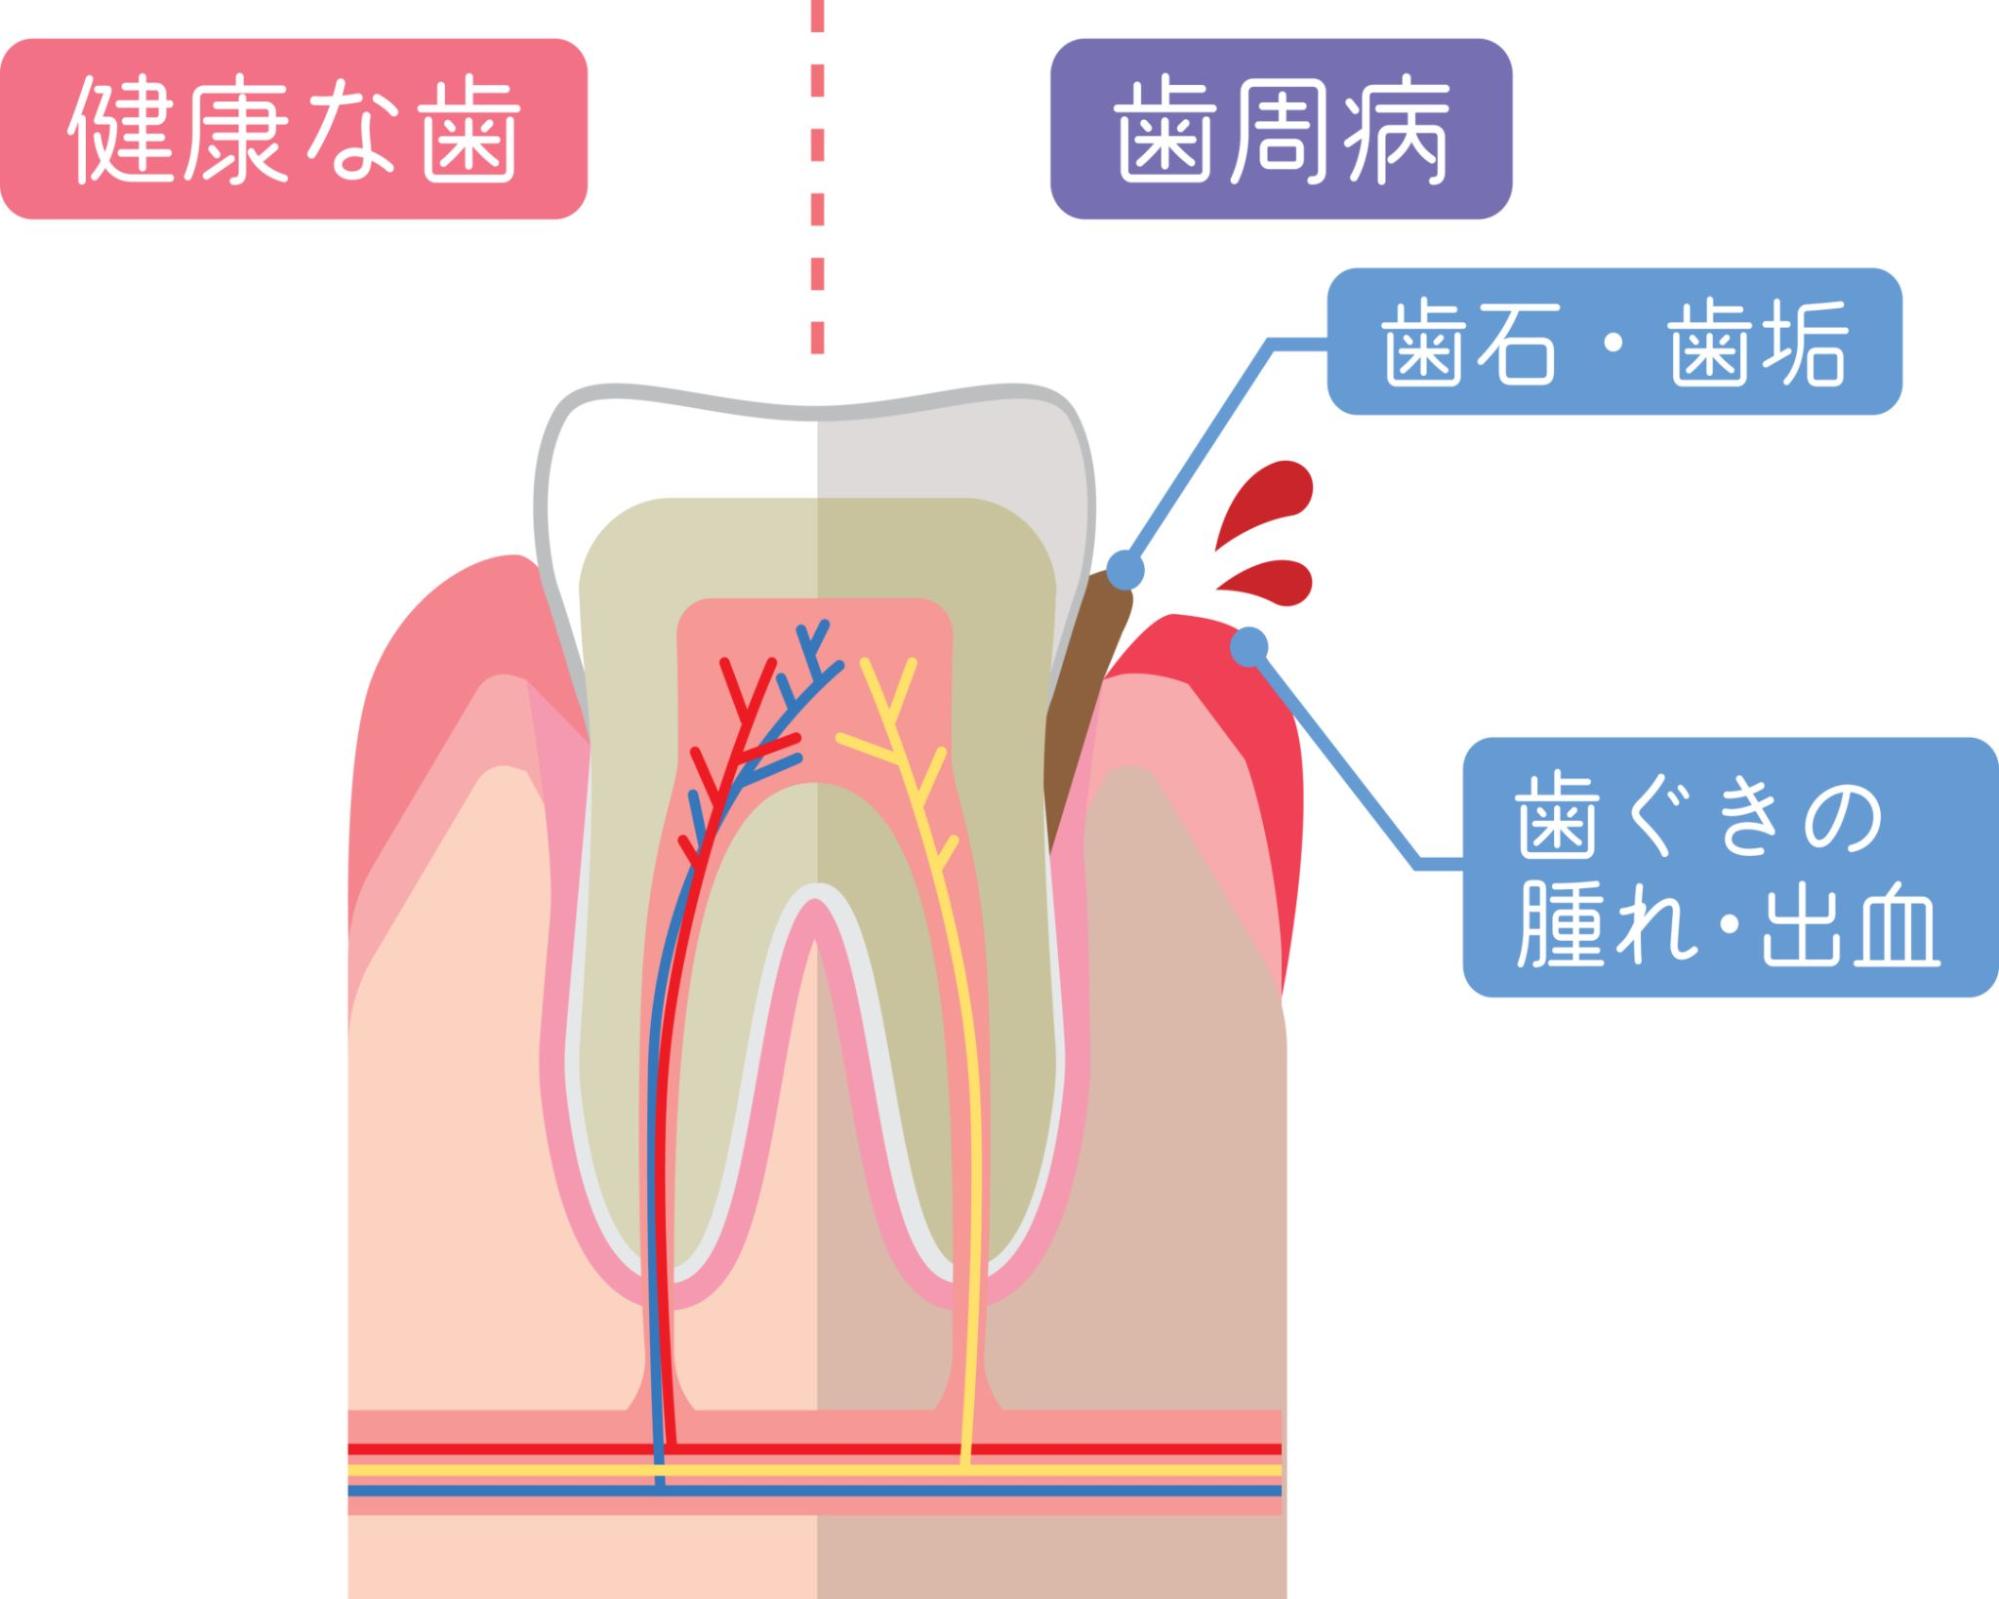

歯周病とは

歯周病は、歯を支える歯茎や骨などの組織が細菌感染によって炎症を起こし、徐々に破壊されていく病気です。日本人が歯を失う原因の第一位であり、成人の約8割が何らかの形で歯周病にかかっているといわれています。

初期段階では歯茎の腫れや出血といった軽い症状から始まりますが、放置すると歯を支える骨が溶けて歯がぐらぐらと動くようになり、最終的には抜歯が必要になることもあります。また、歯周病は口の中だけの問題ではなく、全身の健康にも影響を及ぼすことが明らかになっています。

歯周病の原因

歯周病の直接的な原因は、歯と歯茎の境目に溜まるプラーク(歯垢)です。プラークは細菌の塊であり、この中に含まれる歯周病菌が毒素を出すことで歯茎に炎症が起こります。

プラークは食後およそ8時間で形成され始め、放置すると48時間ほどで石灰化して歯石になります。歯石は歯ブラシでは取り除けないほど硬く、表面がざらざらしているためさらにプラークが付着しやすくなります。この悪循環により、歯周病は徐々に進行していきます。